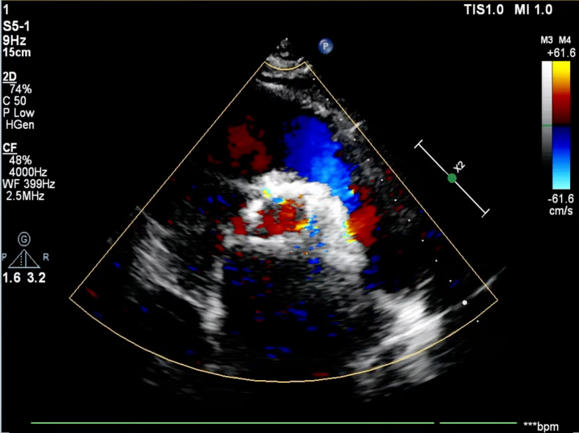

手术采用22 mm TaurusAtlas球囊进行预扩,植入AV23TaurusNXT主动脉瓣。第一次释放后位置偏高,瓣膜完全回收。第二次释放到工作位,检测左右冠血流灌注情况,考虑左瓣叶的瓣尖钙化影响左冠脉血流,使用第二次回收后,预置LCA保护。之后再次释放瓣膜至工作位,在GuidezillaII支撑保护下送 4.0×18mm 支架至 LAD 近段,之后瓣膜精准释放,后用22mm TaurusAtlas球囊后扩。术后即刻经胸超声心动图评估显示少量瓣周漏,平均跨瓣压差为10mmHg,主动脉瓣口峰值流速为2.3m/s,有效瓣口面积为1.80cm²,血流动力学指标理想。

血流动力学改善,瓣膜形态良好,少量瓣周漏